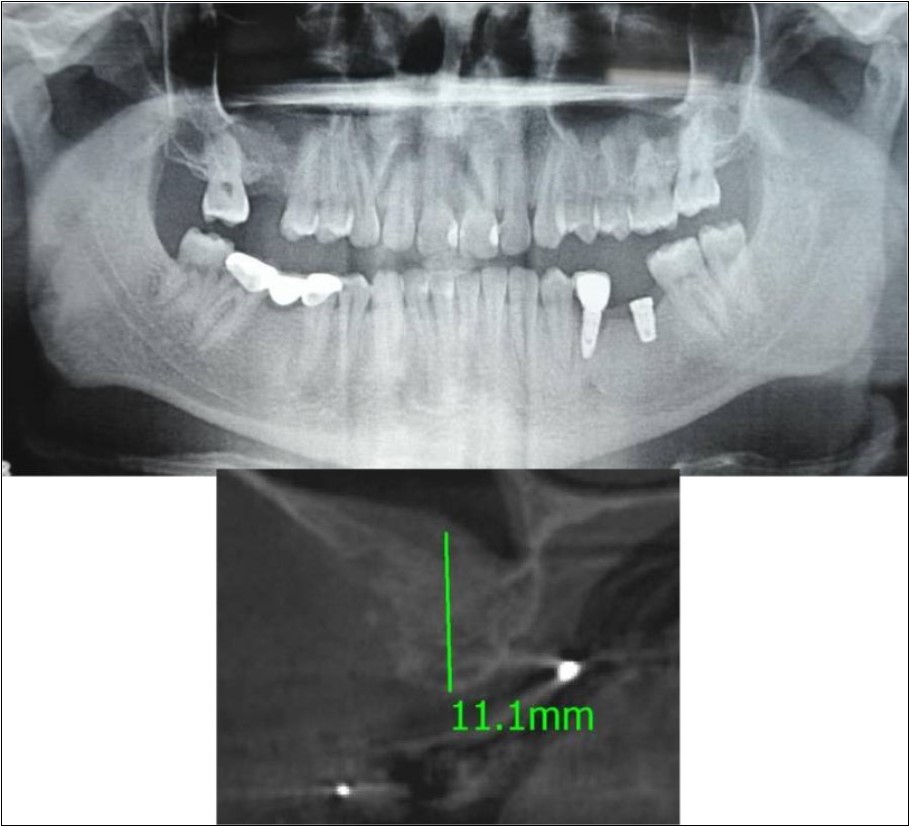

Figure 17.a,b. Pre-treatment OPG and cross section of CBCT showing residual alveolar bone height for Case No.6;

Figure 18.(a,b) Post-treatment OPG and cross section of CBCT showing residual alveolar bone height for Case No.6;